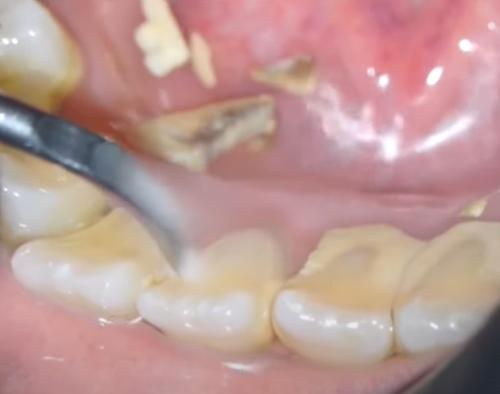

그러나 치석은 보이는 것보다 훨씬 더 완고하다는 것을 알 수 있습니다. 이 경우 치과의사 또는 치과위생사가 이를 제거해야 합니다.

치과 위생을 유지하는 것의 일부는 전문적인 청소를 위한 정기적인 치과 방문입니다. 이상적으로는 1년에 두 번(6개월에 한 번) 이 작업을 수행해야 합니다. 그러나 치석 축적이 반복되는 문제인 경우 더 자주 갈 수 있습니다.

치과의사가 치아에서 치석을 제거하는 가장 안전하고 빠르며 효과적인 방법임에도 불구하고 많은 사람들이 전문적인 세척을 받기를 꺼립니다.